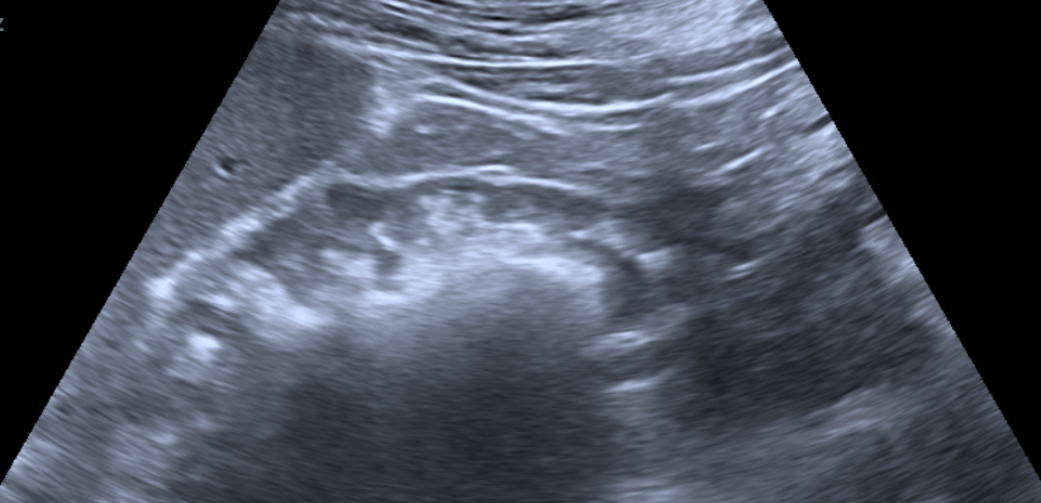

术前,超声定位见结石充满肾盂、肾盏,肾脏几乎无积水,这对经皮肾穿刺通道的建立带来了很大的挑战,导丝极易滑脱或者穿透对侧肾实质,进而造成操作通道的丢失及肾脏大出血等严重并发症。

术中,周守军主任医师选择肾脏中盏背侧后组为穿刺路径,超声实时引导下,精准穿刺至目标肾盏,整个穿刺过程一气呵成,通过F20单通道配合第五代EMS(瑞士EMS超声弹道碎石系统)一次性完成超声碎石取石手术,术后复查无明显结石残留。通过此次手术,医生借由一个大小仅7mm的切口,就彻底清除了左侧肾内6.8cm大的结石,解除了困扰患者2年多的烦恼,患者对手术结果表示非常满意。